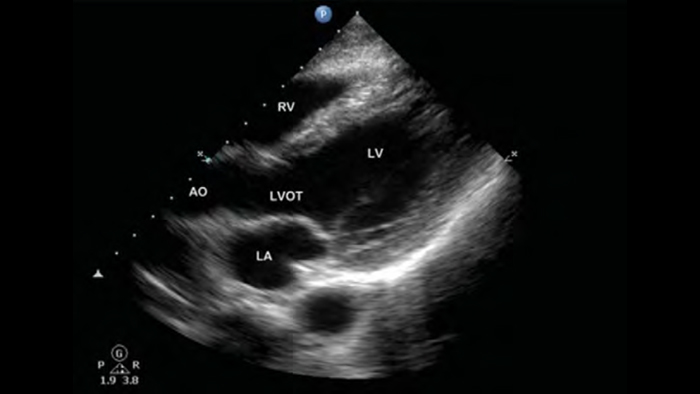

Pre-klinische point-of-care-hartechografie: longembolie